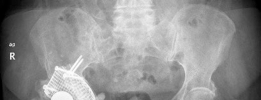

Initial plain radiographs, including an anteroposterior pelvis and cross-table lateral of the right hip, were obtained and meticulously reviewed. The AP pelvis demonstrated severe superior and medial migration of the cementless acetabular component. The hemispherical cup was definitively loose, exhibiting progressive, contiguous periprosthetic radiolucent lines exceeding 2 mm across all three DeLee and Charnley zones. This pattern is the radiographic hallmark of aseptic loosening driven by particulate osteolysis.

There was evidence of extensive acetabular bone loss, particularly localized to the superior dome (ilium) and the medial wall. The medial migration of the component resulted in violation of the Kohler line (ilioischial line), confirming the presence of protrusio acetabuli. The teardrop, a critical radiographic landmark representing the inferior aspect of the acetabular fossa, appeared attenuated but not completely obliterated.

Conversely, the femoral component appeared well-fixed and stable radiographically. There was no evidence of subsidence, pedestal formation at the distal tip, or significant periprosthetic radiolucencies in the Gruen zones. The proximal porous coating appeared to have robust osteointegration, and the diaphyseal fit remained isthmic.